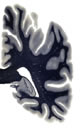

Hi-Resolution Sections · Cells (Nissl Staining) · Virtual Microscopy

Frontal sections (Nissl) from the Atlas Brain: Gallery Slice Single